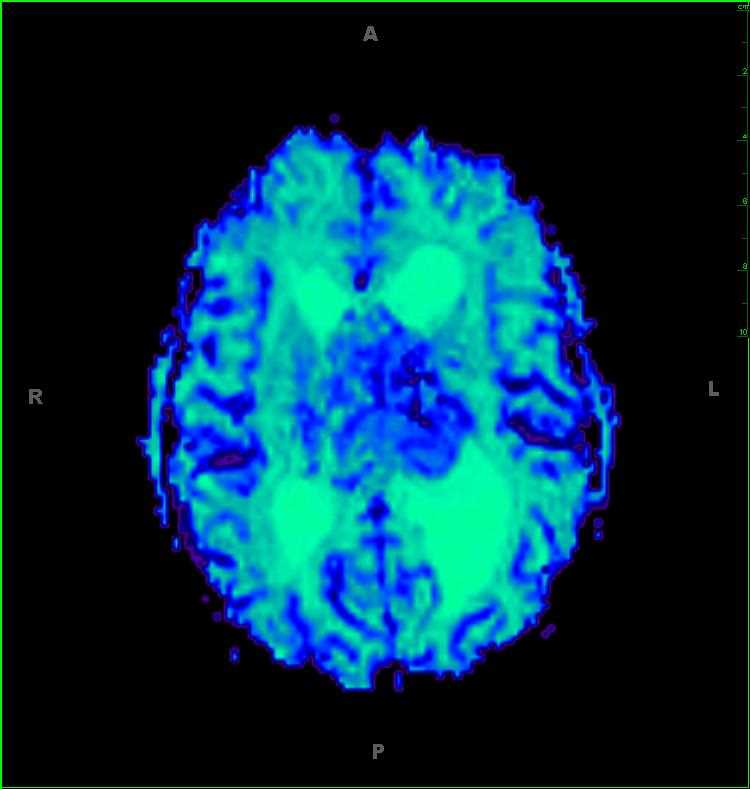

45-year-old female with chronic headaches. There is a well circumscribed, solid and cystic, T1-hypointense, T2/FLAIR-hyperintense, enhancing mass with increased blood volume centered on the foramen of Magendie. The mass enlarges the foramen spilling into both the cisterna magna and fourth ventricle. The differential includes ependymoma, subependymoma, choroid plexus papilloma, meningioma and metastatic disease, given the patients age. This was an anaplastic ependymoma. Ependymomas represent slow growing tumors of the ependymal cells. 2/3 are infratentorial with most centered in the fourth ventricle. Calcifications are common, and cysts and/or hemorrhage may be present. Despite the tumor having low cellularity, ADC values are typically low.